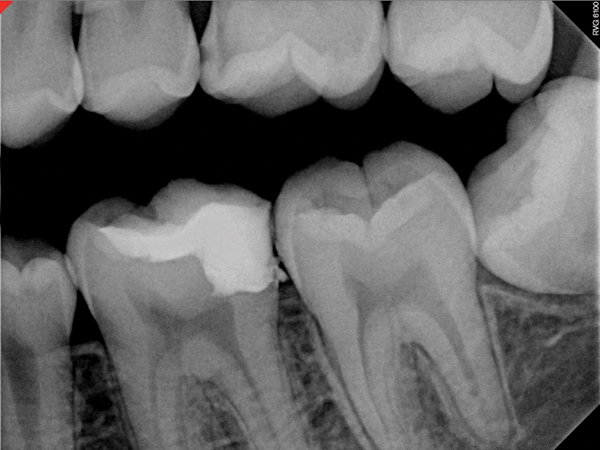

Fig 11. Preoperative radiograph. Courtesy of Dr. Guillaume Jouanny.

Figure 11

Fig 12. Postoperative radiography after full pulpotomy was performed. Courtesy of Dr. Guillaume Jouanny.

Figure 12

Fig 13. Tooth was asymptomatic at 1-year follow-up. Courtesy of Dr. Guillaume Jouanny.

Figure 13

Fig 14. Contralateral tooth at 1-year follow-up. Courtesy of Dr. Guillaume Jouanny.

Figure 14

In this case, the tooth tested vital but showed clinical signs of irreversible pulpitis. Treatment with a full pulpotomy was chosen to improve the chances the remaining pulp would survive and remain healthy. The preoperative radiograph in Figure 11 shows extensive caries in the tooth and a slightly widened apical periodontal ligament. A full pulpotomy was performed using the BC putty (Figure 12). After the putty set, a coronal restoration was placed, and an immediate postoperative radiograph was taken and viewed. At the 1-year follow-up, the tooth was asymptomatic, and the radiograph showed continued root development (Figure 13), a healthy apical periodontium, and, importantly, no calcifications in the remaining pulp (as is often seen with a calcium hydroxide therapy). A radiograph taken of the contra-lateral tooth showed similar root development (Figure 14).